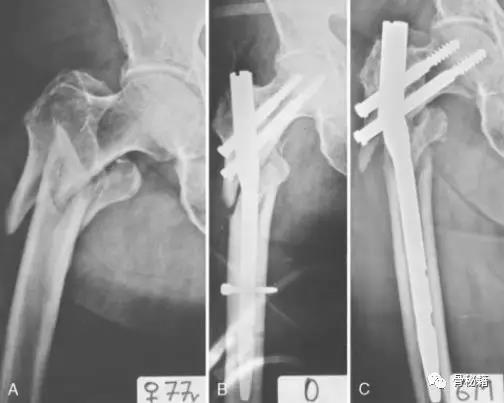

一个双膦酸盐治疗5年的患者粗隆下非典型骨折

采用了髓内钉固定,术后一年内固定失效

更换了DCS+植骨固定,术后四个月又发现了内固定失效再次更换了更长的DCS

这次的固定能成功吗?